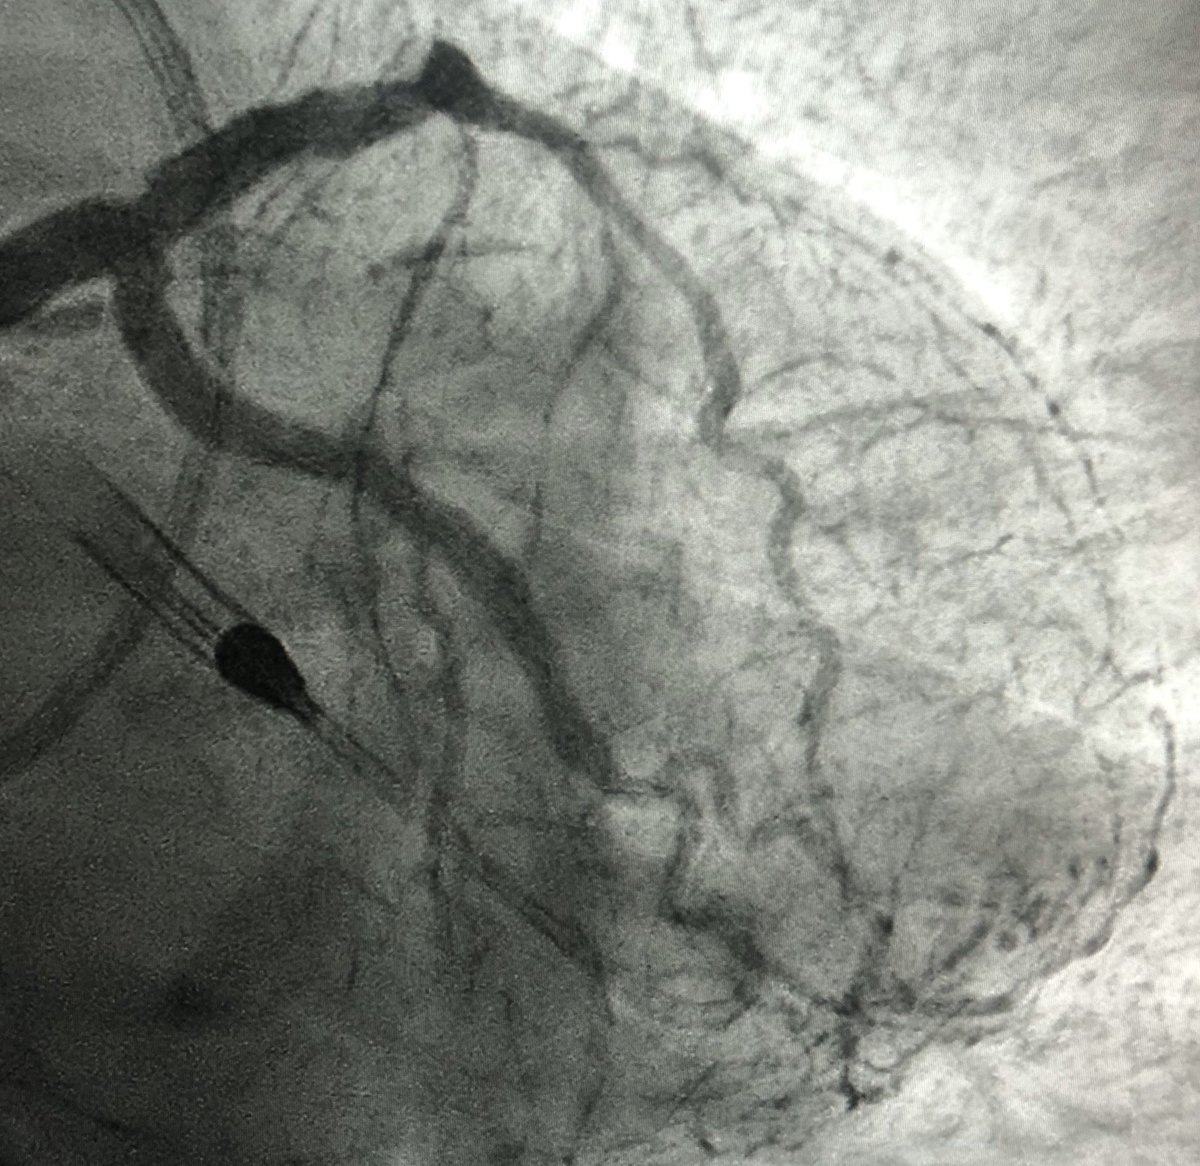

62 y/o male presents with NSTEMI. Boarded for cath in am. Prior to cath VT arrest and on vasopressors Findings at cath, severe LAD, CTO LCx, CTO RCA. LVEDP 34mmhg, EF 10%. Severe PAD. Rx with IC fellow sticks #PercAx Impella and IVUS guided revasc. Now off vasopressors.

DrAmirKaki's tweet image. 62 y/o male presents with NSTEMI.  Boarded for cath in am.  Prior to cath VT arrest and on vasopressors Findings at cath, severe LAD, CTO LCx, CTO RCA.  LVEDP 34mmhg, EF 10%.  Severe PAD.  Rx with IC fellow sticks #PercAx Impella and IVUS guided revasc.  Now off vasopressors.